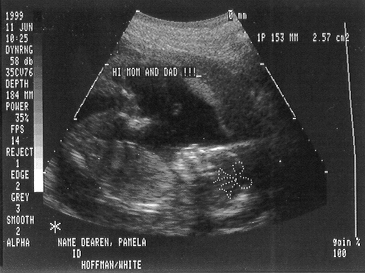

This is me at 20 weeks. Mom was ecstatic to find out I was a girl!